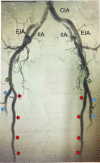

Peripheral arterial disease as seen on X-ray and arteriography